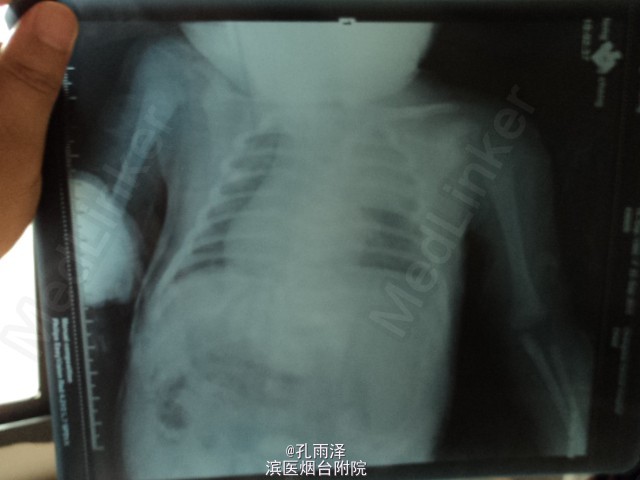

病史:患儿女,1d,因“气促、喉鸣1d”入新生儿重症监护室。患儿足月剖宫产分娩,Apgar评分:1min6分,5min9分,羊水正常,出生体质量4000g。生后口周紫绀、气促、喉鸣。

查体:足月新生儿貌,反应稍差,躯干、四肢可见散在针尖大小出血点,三凹征(+),双肺呼吸音粗糙,对称,可闻及吸气相喘鸣音及粗湿啰音。 实验室检查:血气分析:pH7.319,氧分压(P02)90mm.Hg,二氧化碳分压46.5mmHg,BE-2mmo]/L。血常规:白细胞(WBC)20.57×109/L,N 83.80%。尿钙试验(+)。Pr系列:血浆凝血酶原时间15.2s,活化部分凝血活酶时间53.08,血浆凝血酶时间测定20.7s。

诊断:(1)气管憩室;(2)新生儿肺炎;(3)巨大儿。 处理:予心电监护,维持水、电解质、酸碱平衡,供给足够的热卡,抗感染、制酸止血、营养心肌等治疗。住院2d病情控制出院。嘱定期复诊。